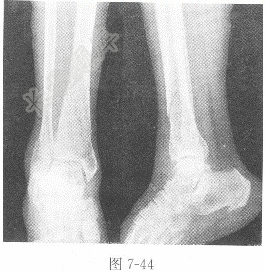

试题详情单项选择题男性,60岁,摔伤20min,下肢X线图像见图7-44,X线诊断为( )。 A、右胫腓骨骨折B、右股骨骨折C、右胫骨骨折D、右腓骨骨折正确答案:关注下方微信公众号,搜题查看答案热门试题题见图6-11。肝囊肿女性,30岁,心悸、头晕2年,X线图像见急性硬膜下血肿糖链抗原19-9(CA19-9)阵发性室性心动过速题见图6-14。 血清脂蛋白雌激素受体(ER)与孕激素受体(PR)如何判断房性期前收缩代偿间歇是否完全?正常胸部正位片动脉血二氧化碳分压(PaCO2)肾癌血清尿酸(UA)测定活化部分凝血活酶时间(AFTT)男性,20岁,咳血半小时,X线图像见图7膀胱结石典型浸润型肺结核铁蛋白(SF)血清总胆红素(STB)和结合胆红素(CB